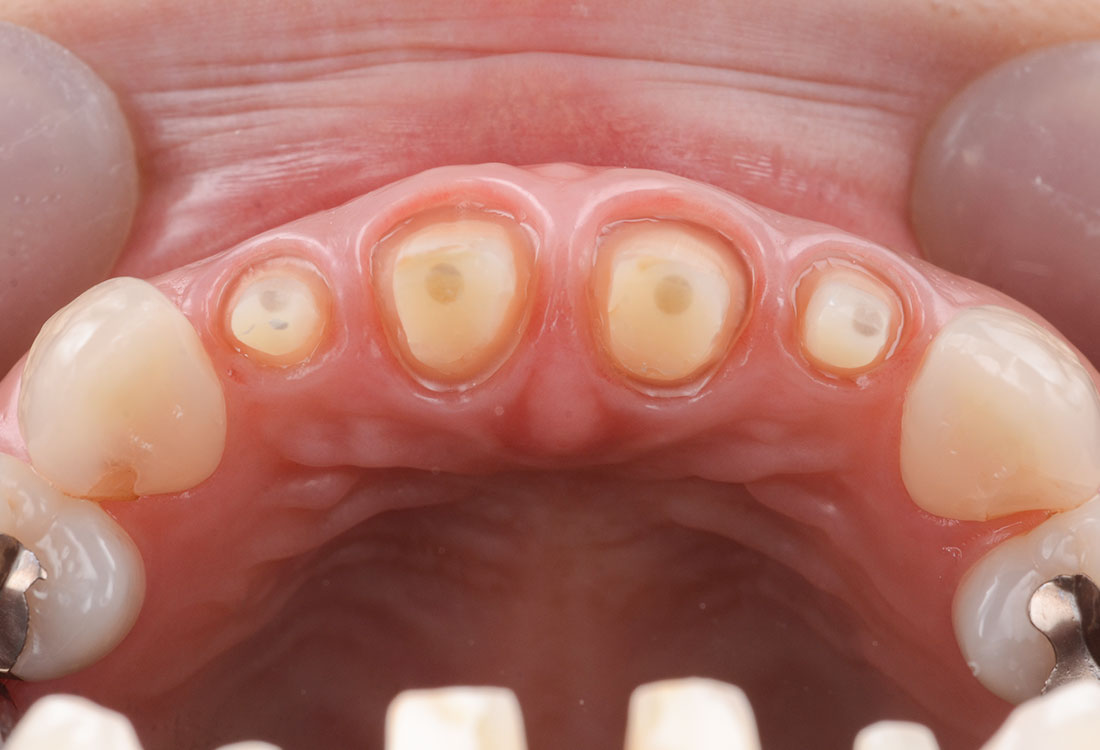

治療内容

模型を作成して最終的な形を模索します。

ファイバーコアで神経のない歯に土台を作ります。

ファイバーコアは保険治療で使われるメタルコアと異なり白く、被せ物が透けて黒く見えません。

土台になる歯の形を整えて最終的な形の模型を作ります。